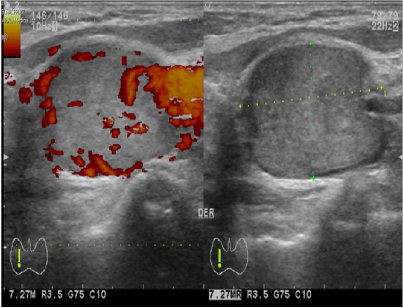

La evaluación ecográfica concluye la presencia de un nódulo en el lecho tiroideo derecho con las siguientes características: heterogéneo, hipoecoico, de bordes bien definidos y dimensiones de 23 x 16 mm (figura 1) sin microcalcificaciones, flujo doppler periférico positivo y ausencia de adenomegalias cervicales (figura 2).

No existen reportes de casos diagnosticados por estudios de imágenes. El ultrasonido con efecto doppler reporta una lesión nodular, sólida, hipoecoica, bien delimitada de tamaño variable e hipervascularizada, características que lo hacen indistinguible de las neoplasias tiroideas comunes. El CT-PET, TAC y gammagrafía tiroidea no son estudios de rutina, y sus hallazgos tampoco permiten distinguirles de otras neoplasias tiroideas15,16.